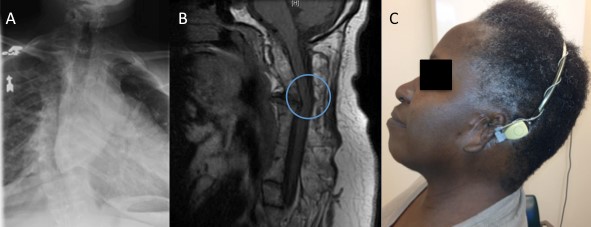

Her height was 4 feet 11 inches, weight 144 pounds, body mass index of 29.1. She was alert, pleasant and able to provide a clear history. Her neck was short, with limited extension. Posterior hairline was low, and she had external auditory canal malformation (Figure 2C). Oral airway was Mallampatti IV, tonsils 2+. Lungs were clear to auscultation. Neurologic exam was normal except that strength was 4/5 for shoulder abduction bilaterally, right elbow flexion, and hip flexion bilaterally. Mirror movements (voluntary/active movements of one extremity that are mimicked by involuntary/passive movements in the opposite extremity) were not observed.

Given the severity of her sleep disordered breathing, a neck radiograph was ordered. On lateral view, fusion of cervical vertebrae C1-C3 was noted (Figure 1). A chest radiograph showed dextro-scoliosis without thoracic vertebral fusion (Figure 2A). Magnetic resonance imaging (MRI) of the cervical spine revealed fusion of the first three cervical vertebrae with degenerative changes throughout the cervical vertebrae, protrusion into the cervical canal, and reversal of normal cervical curvature (Figure 2B). Arnold-Chiari malformation was not seen. Spinal cord signal intensity was normal. MRI of the brain, and brainstem was normal.

Figure 2: Imaging of this patient with Klippel-Feil Syndrome. A: Thoracic spinal column radiograph showing dextro-scoliosis without thoracic vertebral fusion. B: Sagittal T1 weighted image magnetic resonance imaging of the cervical spine showing fusion of the first three cervical vertebrae, protrusion into the cervical canal (circle), and reversal of the normal cervical curvature. C: Photograph of the patient attempting to extend her neck, demonstrating limited range of motion. Note the under-developed external ear (microtia).